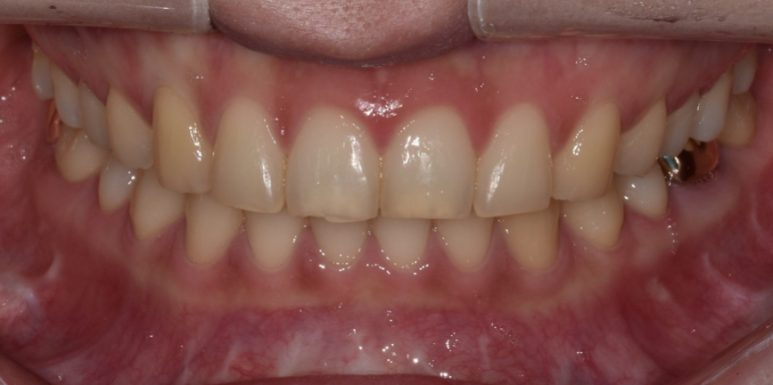

환자분은 교정 후 유지 장치를 착용하고 계신 상태이며,

치아배열은 고르지만 치아 모양과 색상이 마음에 들지 않아 라미네이트 시술을 위해 내원해 주셨습니다.

환자분 역시 삭제량이 많은 것을 원하지 않으셨기에 대문니 끝 파절된 부분과 보철물 부착을 위한 최소삭제로 진행을 도와드렸습니다.

(전) 2022-08-02, (후) 2022-08-11

평소 이갈이가 있다고 하셔서 이갈이 장치 제작 및 사용을 권장해 드렸는데요.

지속적인 이갈이로 보철물에 힘이 가해지면, 라미네이트가 깨질 우려가 있기 때문입니다.

따라서 평소 이갈이를 하시는 분들은 시술 전 담당 주치의에게 미리 말씀하시고, 장치를 제작하여 착용하시는 것이 좋습니다.